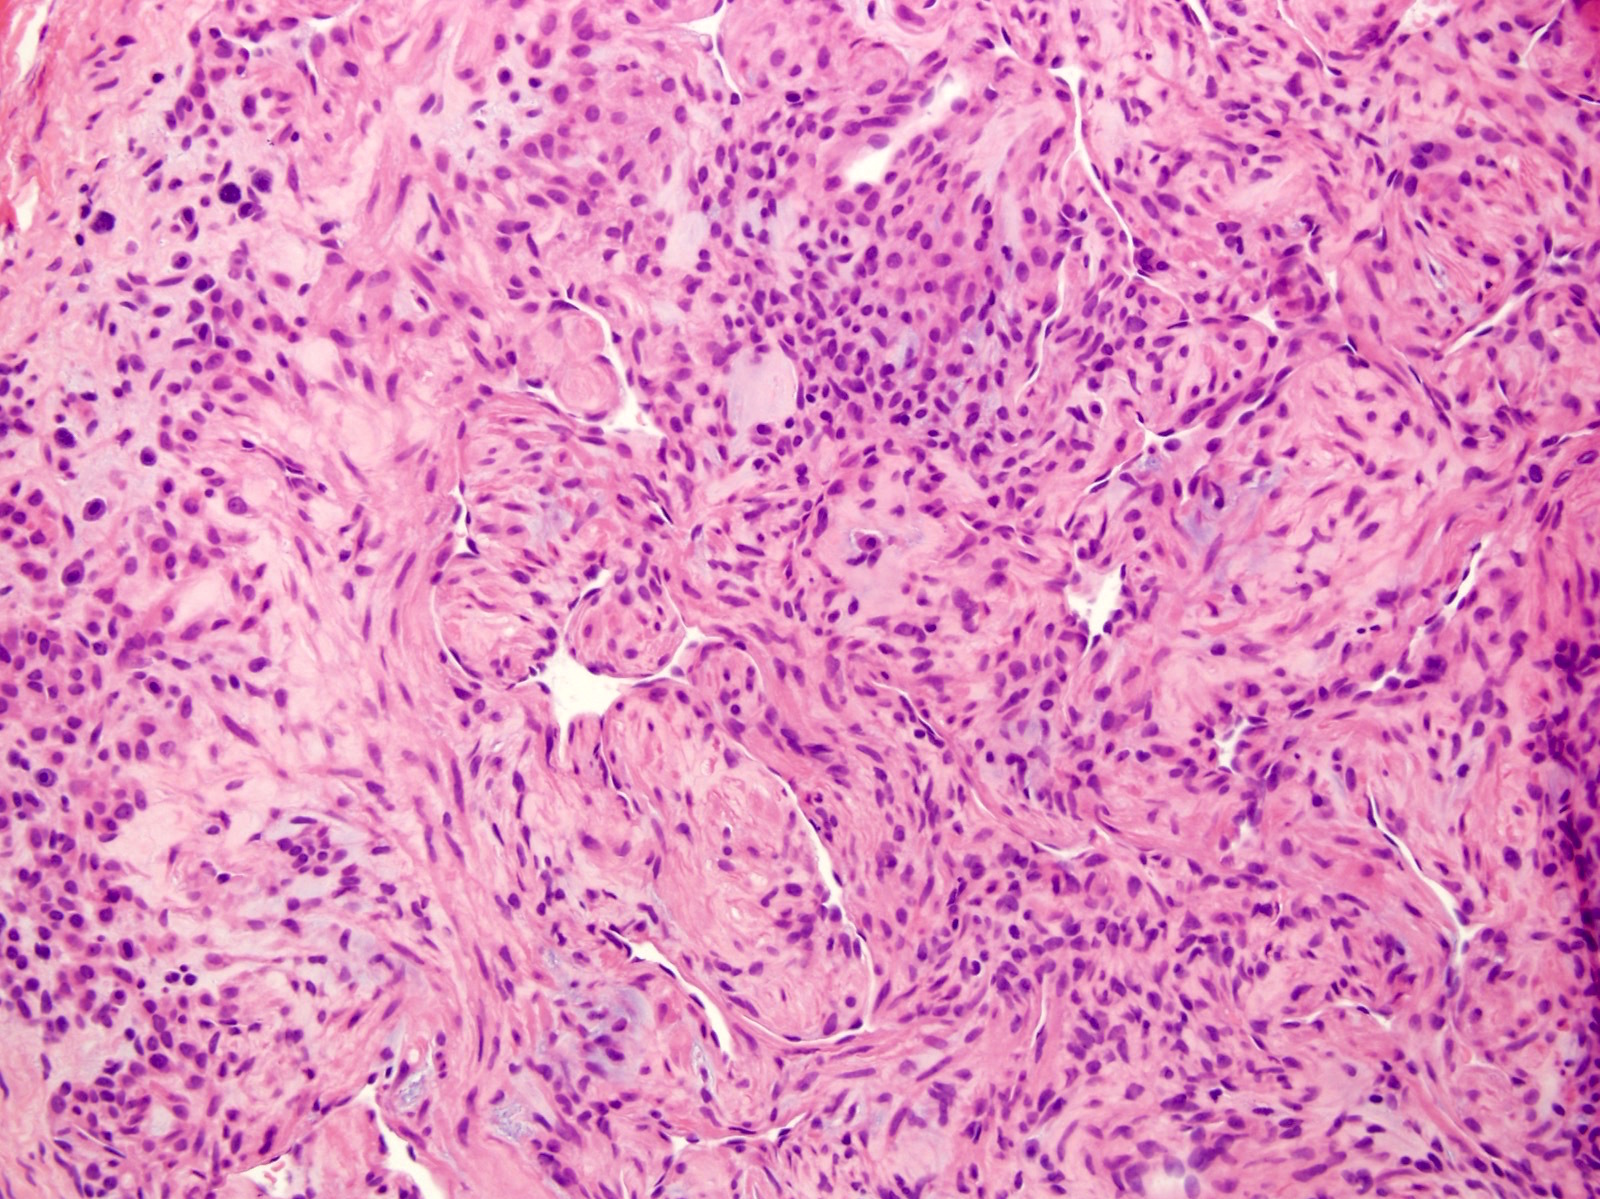

Microscopic (histologic) description

- Well circumscribed mass composed of 3 components: glomus cells, vasculature and smooth muscle cells

- Solid glomus tumor (75% of cases): predominantly glomus cells, poor vasculature and rare smooth muscle cells

- Glomangioma (20% of cases): tumors with prominent vascular component

- Glomangiomyoma (5% of cases): tumors with prominent vascular and smooth muscle components

- Rare variants have microscopically infiltrative and diffuse growth and are known as glomangiomatosis

- Benign glomus tumors (Arch Pathol Lab Med 2008;132:1448):

- Branching capillary sized vessels lined by endothelial cells surrounded by collars of uniform glomus cells forming nests, sheets and trabeculae in a hyalinized or myxoid stroma

- Glomus cell has a round shape with indistinct borders with a rounded, sharply punched out nucleus in an amphophilic to eosinophilic cytoplasm

- Chromatin is homogenous and bland with inconspicuous nucleoli

- Very rare mitoses

Microscopic (histologic) images

Contributed by Farres Obeidin, M.D.

Case #289

Case #238